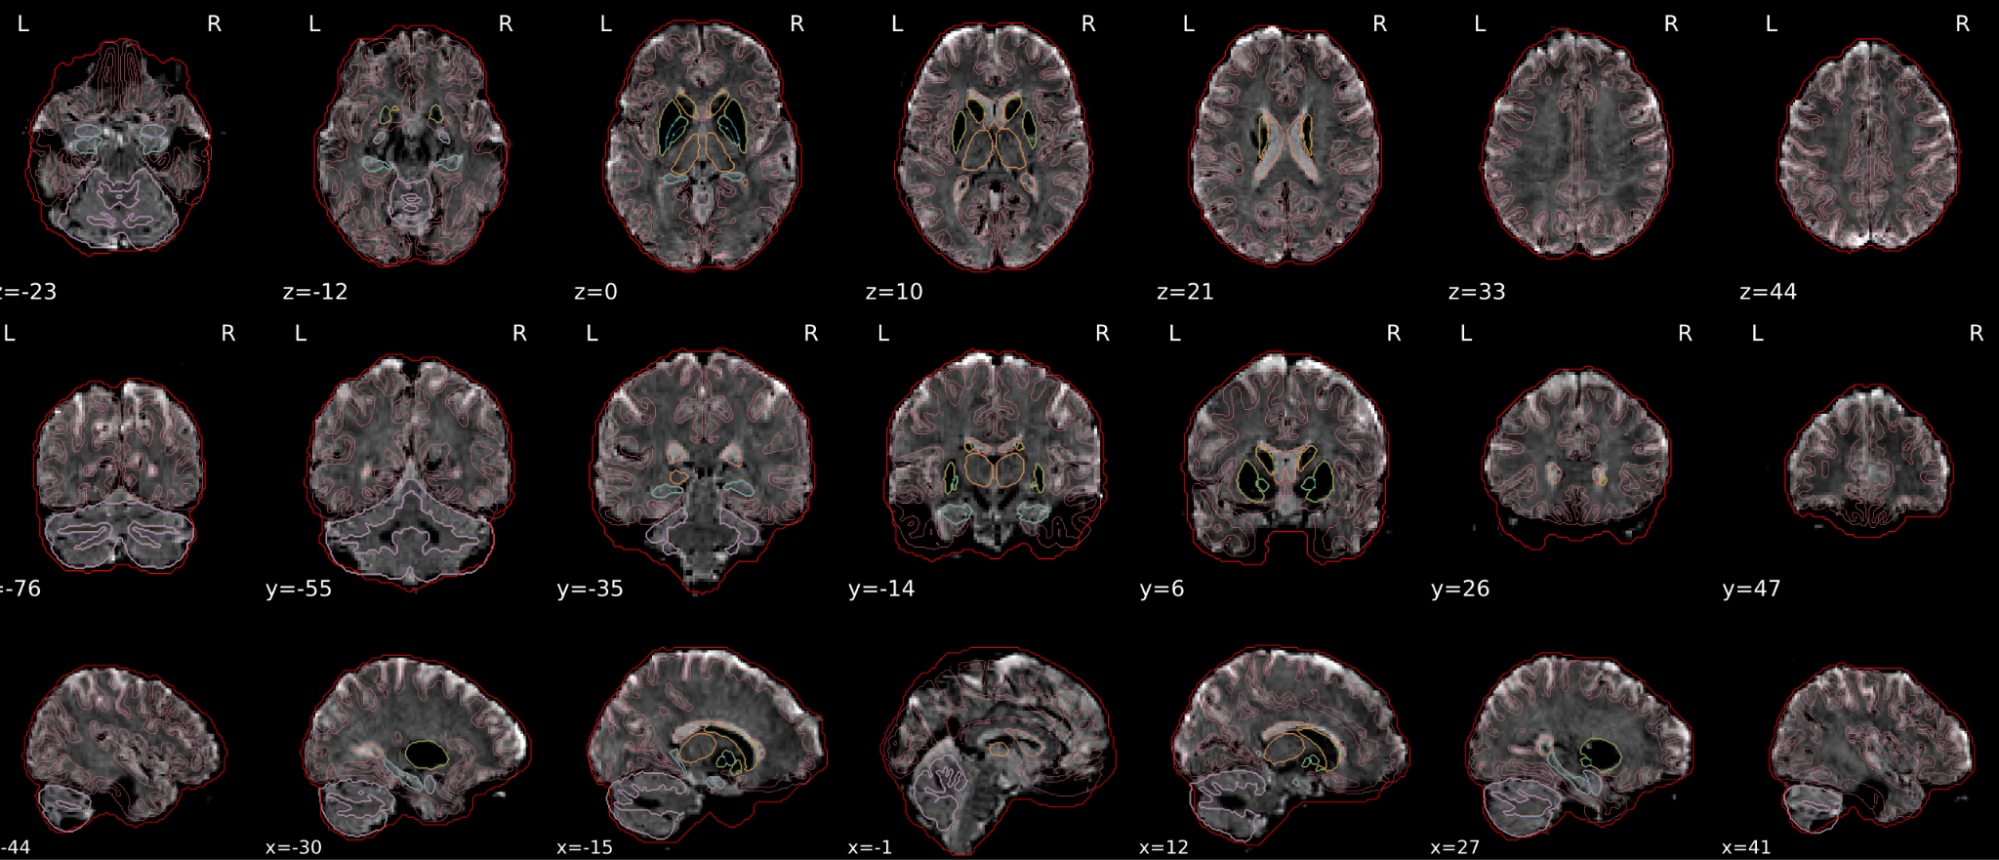

EPI spatial normalisation

This QC step shows the registration of the EPI image to MNI space.

Example of a good subject

- If the registration performed well, you should see an overlap (i.e., correspondence of structures) between the MNI template and the EPI registered to the MNI space.

- If parts of the brain are missing due to the scanner field of view, this is fine. For example, the cerebellum may be cut off for a participant with a large head.

Example of a bad subject

- In case of poor registration, you should see a misalignment of the EPI and the MNI template

Summary

| good | bad |

|---|---|

| Overlap (i.e. match of structures) between the MNI template and the EPI registered in the MNI space | Misalignment of the EPI and the MNI template |

| If parts of the brain are missing because the field of view of the scanner is limited, the EPI spatial normalisation does not have to be excluded e.g. cerebellum cut off in person with large head |

If parts of the brain are missing because the field of view of the scanner is limited, the EPI spatial normalisation does not have to be excluded (e.g. cerebellum cut off in person with large head)